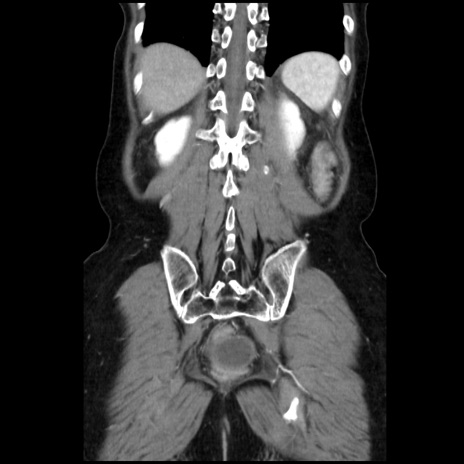

症例32(冠状断像)

【症例】40歳代 女性

【主訴】上腹部痛、嘔気・嘔吐

【現病歴】約9時間前頃から急に上腹部痛、嘔気、嘔吐が出現。改善しないため救急要請。

【既往歴】子宮頚癌(広汎子宮全摘術、放射線療法)、腸閉塞

【身体所見】腹部:平坦、軟、腸雑音亢進、上腹部を中心に腹部全体に圧痛あり。

【データ】WBC 8400、CRP 0.03